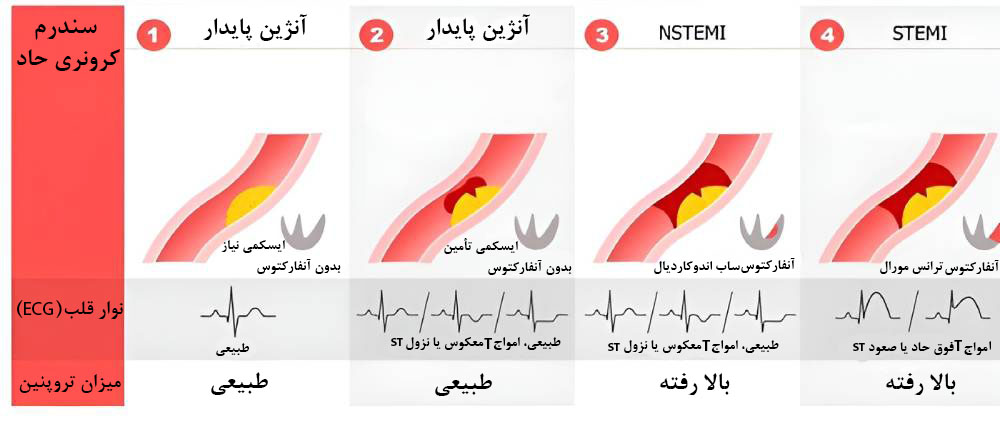

انواع سکته قلبی

حملۀ قلبی نوعی سندرم کرونری حاد (ACS) است که با انسداد قابلتوجه شریانهای کرونری همراه است.

چهار نوع اصلی ACS عبارت است از:

- آنژین پایدار

- آنژین ناپایدار

- آنفارکتوس میوکارد بدون صعود قطعۀ ST (NSTEMI)

- آنفارکتوس میوکارد با صعود قطعۀ ST (STEMI)

آنژین پایدار

آنژین پایدار (آنژین پکتوریس یا آنژین صدری) نوعی درد قفسۀ سینه است. این درد وقتی شروع میشود که عضلۀ قلب به اکسیژنی بیشتر از حد معمول نیاز داشته باشد، اما اکسیژن موردنیازش را به علت بیماری قلبی در آن لحظه دریافت نکند. این اتفاق زمانی رخ میدهد که هوا سرد باشد یا در حال ورزش باشید. آنژین پایدار نوعی درد موقت قفسه سینه است، اما میتواند در نهایت به سندرم کرونری حاد منجر شود.

آنژین ناپایدار یا سکته قلبی خاموش یا پنهان

آنژین ناپایدار که با اصطلاحات اسپاسم شریان کرونری یا سکته قلبی خاموش نیز شناخته میشود، ممکن است بدون علامت باشد یا علائمش بسیار خفیف باشد. علائم آنژین ناپایدار گاهی با درد عضلانی، سوءهاضمه و… اشتباه گرفته میشود. تنگ شدن شریانهای قلب در حدی که جریان خون متوقف شود یا به شدت کاهش پیدا کند، علت آنژین ناپایدار است. پزشکان فقط از طریق تصویربرداری و آزمایش خون میتوانند سکته قلبی خاموش را تشخیص بدهند.

اسپاسم شریان کرونری با آسیب دائمی همراه نیست. اگرچه سکته قلبی خاموش چندان جدی نیست، خطر سکته قلبی مجدد یا سکتۀ جدیتر را افزایش میدهد.

انسداد ناقص عروق کرونر یا سکته قلبی ناقص (NSTEMI)

NSTEMI به اندازۀ STEMI جدی نیست، چون خونرسانی به قلب نه به صورت کامل، بلکه به صورت جزئی مسدود میشود. در نتیجه بخش کوچکتری از قلب آسیب میبیند. بااینحال NSTEMI همچنان یک مورد اورژانسی جدی محسوب میشود. انسداد ناقص عروق کرونری بدون درمان پیشرفت میکند و به آسیب قلبی جدی یا STEMI تبدیل میشود.

انسداد کامل عروق کرونر یا سکته کامل قلبی (STEMI)

STEMI جدیترین نوع سکته قلبی است که در اثر اختلال بلندمدت در خونرسانی به قلب رخ میدهد. STEMI نتیجۀ انسداد کامل شریان کرونری است که به آسیب گستردۀ بخش بزرگی از قلب منجر میشود. انسداد کامل عروق کرونر همان تصوری است که اکثر مردم از حمله یا سکته قلبی دارند.